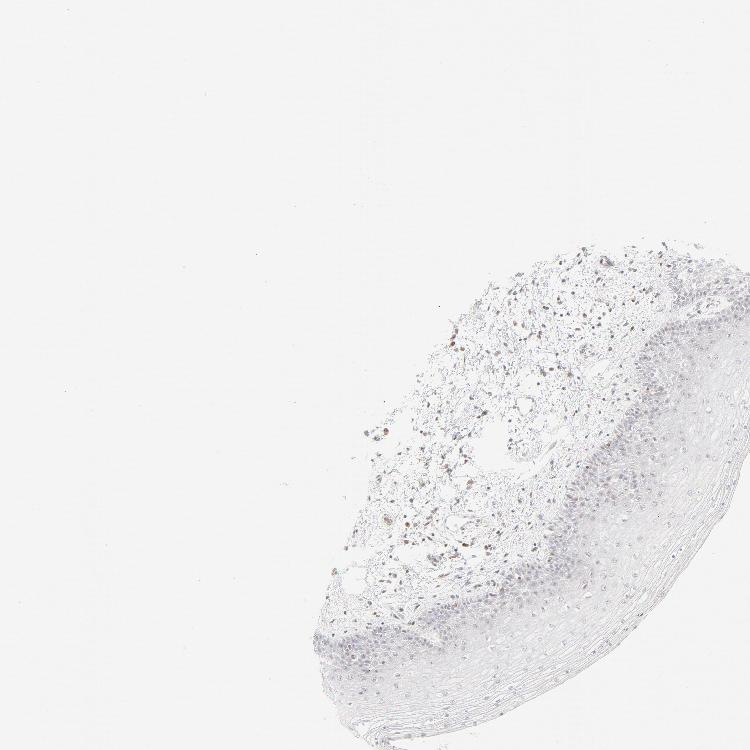

SKIN 1 - Antibody stainingi

Antibody staining in the annotated cell types in the current human tissue is reported as not detected, low, medium, or high, based on conventional immunohistochemistry profiling in selected tissues. This score is based on the combination of the staining intensity and fraction of stained cells.

Each image is clickable and will lead to virtual microscopy that enables deeper exploration of all samples and also displays staining intensity scores, fraction scores and subcellular localization as well as patient and tissue information for each sample.

Antibody HPA048321Antibody CAB003843

Langerhans Not detectedNot detected

Fibroblasts Not detectedNot detected

Keratinocytes LowNot detected

Melanocytes Not detectedNot detected